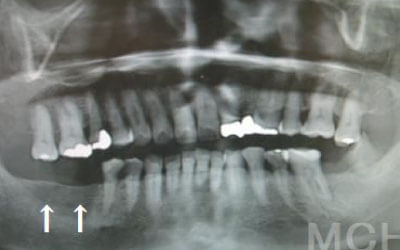

2 歯が傾いてくる、落ちてくる

歯はお互いに支え合ってバランスを保っています。つまり、歯が抜けるとその支えがなくなり、抜けた部分の隣の歯が傾いたり、上の歯が下にずれてくることがあります。